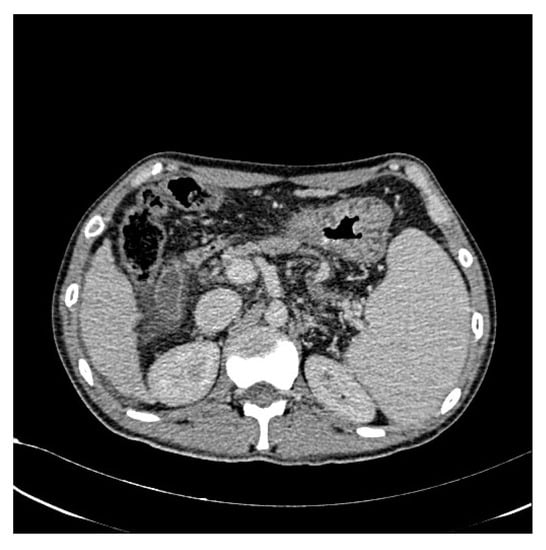

In addition, we used WGIF [38] to enhance the picture and obtain an image with stronger texture features to facilitate training after completion. Figure 3 and Figure 4 illustrate the comparison between the original and enhanced images, showcasing the augmentation of strong classification texture features. The original image, as depicted in Figure 3, demonstrates limited texture details and a relatively lower discriminative potential. However, upon applying advanced image enhancement techniques, as depicted in Figure 4, the texture features undergo substantial enrichment, resulting in heightened discriminative capabilities.

Figure 4.

After increasing the contrast.